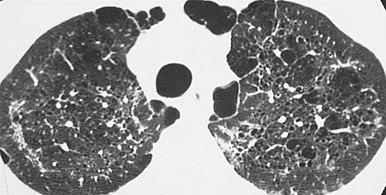

High-resolution computed tomography (HRCT) showing ground-glass attenuation with a geographic or mosaic distribution.[6]

HRCT of cysts of pneumocystis pneumonia. These are usually multiple and bilateral, but range in size, shape and distribution.[6]